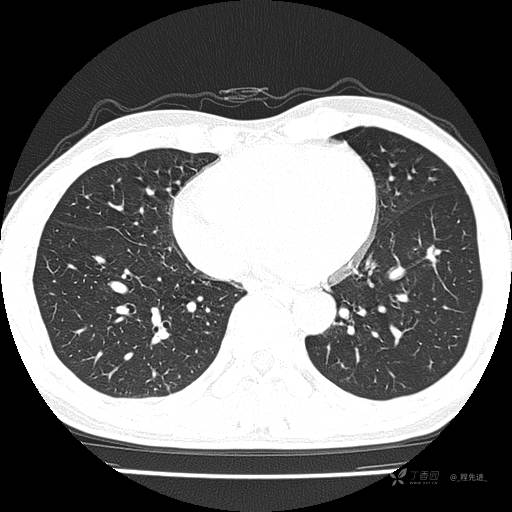

辅助检查:我院门诊胸部CT示:如下。心电图:窦性心律;正常心电图。